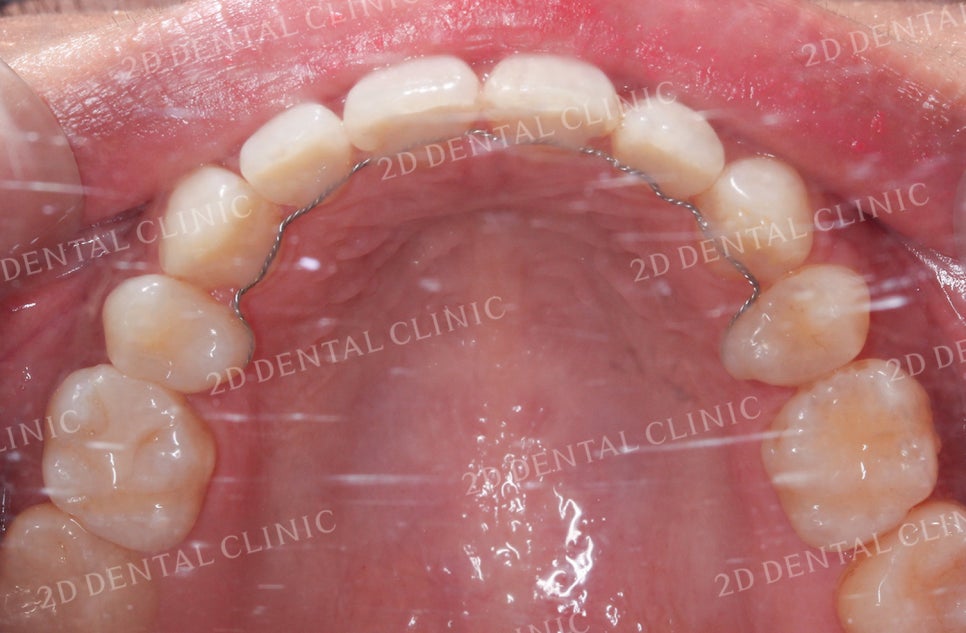

비대칭 돌출앞니 전체교정 전

투디치과(2D치과)

비대칭앞니, 돌출앞니를 전체교정으로 교정하고 싶다면!? by.투디치과(2D치과)

<하악 설측면 사진> <상악 설측면 사진>

상악과 하악의 설측면 사진입니다.

하악의 경우 전치부의 좁은 공간으로 인해

총생이 발견되는데요,

상악 역시 치아가 올바르게 배열되기에

충분한 공간이 확보되지 못한 상태입니다.